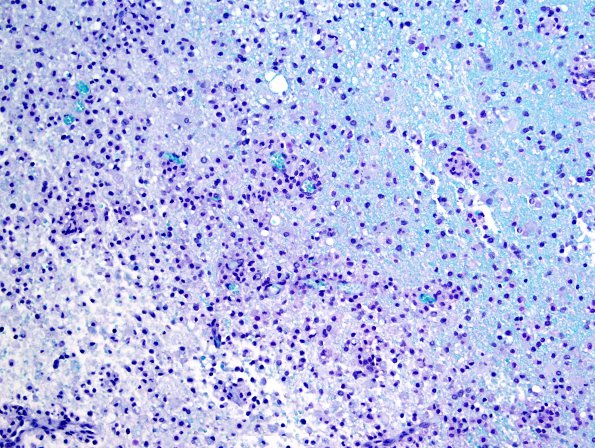

Washington University Experience | MYELIN (IMMUNE-MEDIATED) | Inflammatory Demyelination | 13B4 Inflammatory demyelination (Case 13) LFB-PAS 20X

Higher magnification images of the junction of myelinated and demyelinated areas in multiple sites in the specimen (LFB-PAS)